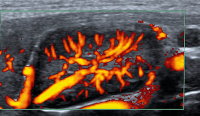

Abbildung 4: PW-Doppler-Analyse. In der Literatur sind immer wieder Hinweise auf die Wichtigkeit der Analyse der Flusskurven intranodaler Arterien zu finden. Die relevanten Schwellenwerte für Resistance Index (RI) oder Pulsatilitätsindex (PI) schwanken in der Literatur stark. Prinzipiell sei bei pathologischen Lymphknoten mit einem eher hohen peripheren Widerstand mit entsprechenden RI und PI zu rechnen. An dieser Stelle seien dem geneigten Leser freie Gedanken zur zeitlichen Durchführbarkeit von Flussmessungen gegebenenfalls mehrerer Lymphknotenarterien mehrerer Lymphknoten mit den passenden Geräteeinstellungen innerhalb der täglichen Routine selbst überlassen. Lymphom.